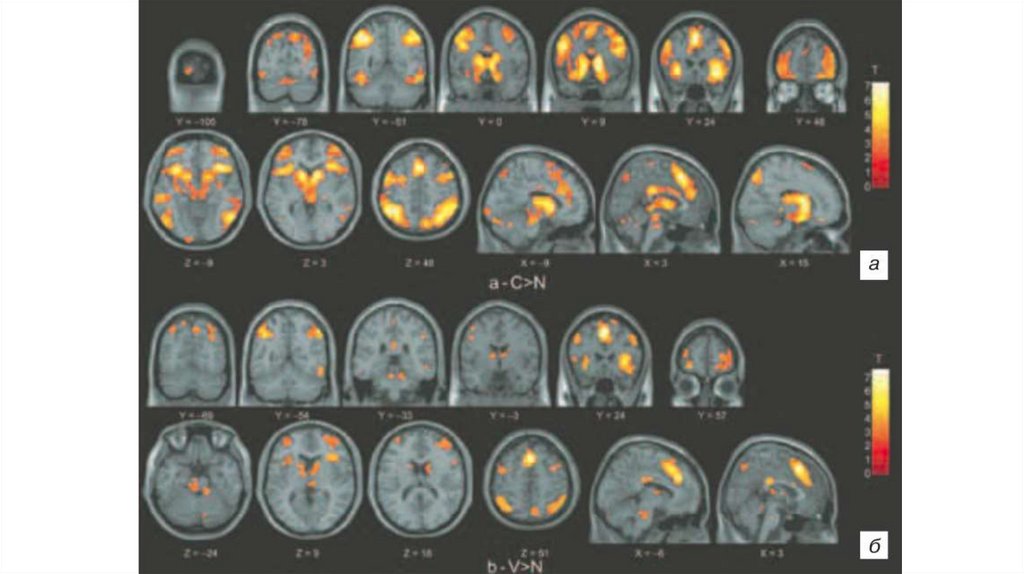

фМРТ

BOLD сигнал

16.

Блочная схема

Связанная с событиями схема